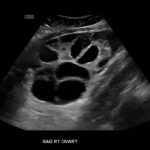

Ovarian hyperstimulation syndrome (OHSS) is a potentially life-threatening complication of assisted reproductive technology (ART). Here, we present the case report of a 30-year-old female undergoing infertility treatment who presented to the emergency department (ED) with nausea and vomiting, abdominal distention, and shortness of breath. On physical exam, she had notable ascites. Computed tomography (CT) of the abdomen and pelvis and pelvic ultrasound (US) revealed significant ascites and enlarged ovaries with multiple cysts. She was diagnosed with severe OHSS and admitted to obstetrics and gynecology (OBGYN) service for five days where she underwent intravenous (IV) hydration and paracentesis. This case report reviews the clinical presentation, categorization, management, and prevention of OHSS and provides examples of imaging findings consistent with the condition.